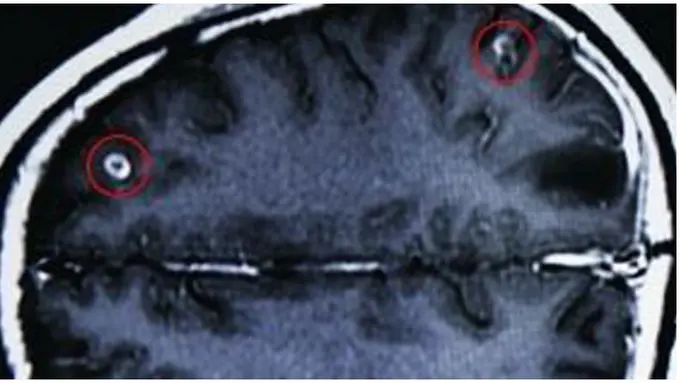

Seperti yang dialami seorang pria di China. Dilansir theglobaldispatch.com, pria yang berasal dari Provinsi Guangxi, China ini dilarikan ke rumah sakit karena mengalami gejala lemah, pusing, dan penglihatan kabur. Tim medis kemudian melakukan CT-scan pada otak pria tersebut dan menemukan 19 ekor cacing pita di dalamnya.

Pria yang tidak disebutkan namanya ini diketahui sering mengonsumsi darah babi segar dalam bentuk sup yang disebut 'Tian Tang Xue'. Larva dan cacing pita dalam darah babi tersebut rupanya masuk ke aliran darahnya dan akhirnya sampai ke bagian otaknya.

Jika tidak mendapatkan perawatan, infeksi cacing pita pada otak akan menyebabkan kerusakan otak dan syaraf yang cukup berat. Keadaan ini juga akan menimbulkan komplikasi berupa epilepsi dan kebutaan. Beruntung pria China tersebut segera ditangani dan dapat sembuh kembali seperti semula.